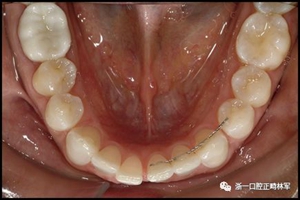

一顆或兩顆尖牙位置的橫向變化可能發(fā)生在與每顆牙齒粘合的小弓絲上,并且在極軟弓絲(圖3)和柔性螺旋弓絲(圖4)上都可以看到。較大直徑的弓絲會產(chǎn)生不同類型的橫向變化。較硬的弓絲與更小的弓絲相比,在尖牙之間產(chǎn)生更多的相關(guān)關(guān)系。弓絲的扭曲會導(dǎo)致尖牙的往復(fù)運(yùn)動和弓形的歪斜(圖5)。相對較硬弓絲的向下偏斜可以通過尖牙產(chǎn)生擴(kuò)張(圖6)。

圖4柔軟的螺旋弓絲保持器,下頜右側(cè)尖牙嚴(yán)重的舌側(cè)傾斜以及下頜左側(cè)尖牙的唇側(cè)移位:A,正面視圖; B,咬合面視圖(John Iaculli博士提供)。